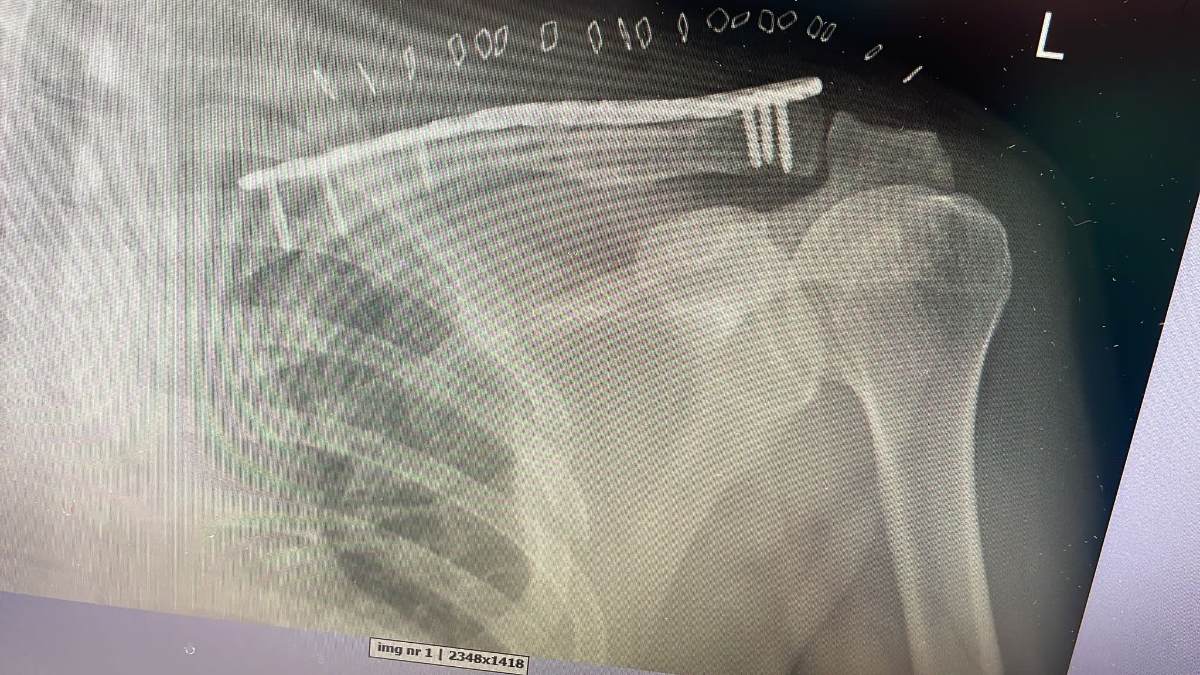

Na zdjęciu przed i po operacji.